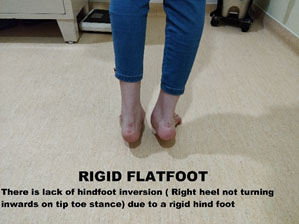

Rigid flat foot- This is a condition where there is limited hindfoot motion even when the individual is standing tiptoed. Either this is due to a bony problem, or there is a fusion of the bones of the foot called a tarsal coalition.

The symptomatic flat foot child usually presents with pain and tiredness of the feet and difficulty to walk long distances because of pain in the feet. The patient will have hindfoot supination as shown before in the tiptoe test to differentiate flexible from rigid flat foot